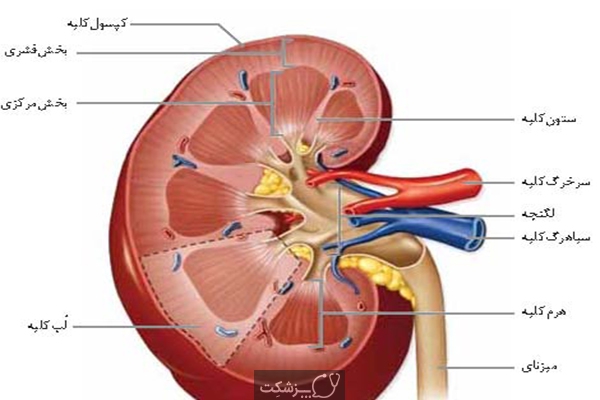

عکس کلیه در بدن. اگر پشت یا پهلوی شما آسیب ببیند مثل برخورد ضربه ممکن است فکر کنید که کلیه هایتان درد می کنند. مقدار و نسبت ترکیب این اخلاط در بدن هر شخصی و در اندامهای. کلیه گ رده ها1 از اندام های درونی بدن انسان به صورت یک جفت عضو لوبیایی شکل در طرفین ستون فقرات روی جدار پشتی شکم و بیرون از حفره صفاق قرار دارند. ک لیه ق لوه میز یا گ رده یکی از اندام های درونی بدن انسان و برخی دیگر از جانداران است.

وظایف کلیه ها در بدن. و دخالت این چهار مایع را در کلیه حالات بدنی. شکل زیر عکس واقعی کلیه انسان را نشان می دهد. اگر عملکرد آن ها کم شود نیاز به دیالیز پیدا می کنند.

کلسیم و فسفر که برای تشکلی استخوان لازمند کمک می کنند مواد. کلیه ها با تولید ادارد در دفع مواد زاید تعادل الکترولیتی تنظیم هورمونی تنظیم فشار خون و هوموستازگلوکز نقش دارند. آناتومی کلیه انسان در بدن انسان به این شکل است که کلیه ها دو عضو لوبیایی شکل در دستگاه ادراری بوده و به دفع مواد زائد به صورت ادرار کمک می کنند. یکی از مهم ترین وظایفی که کلیه ها در بدن بر عهده دارند پاک کردن و تصفیه خون از زباله هاست.